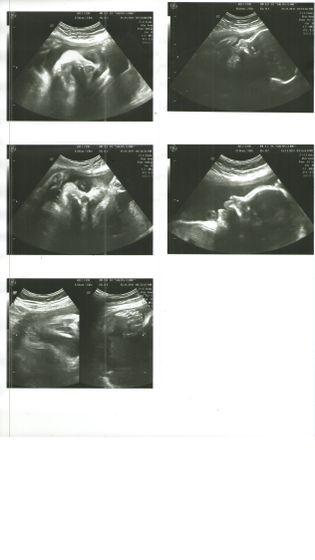

Настроение супер ?Посмотрела на свою Крошку?сказали, что будет красавицей ?И точно девочкой т.к. та все прелести показала ?Сидит она на попе, но воды достаточно чтобы она перевернулась.Весит малышка 1866.Длина шейки 35,6(в 19,6 была 38?).Ещё у неё прям волосики уже длинные ?Вот теперь у меня дилемма ? т.к. Я досихпор работаю и у меня есть возможность ещё поработать в декабре, но работа сидячая.Может она на попе сидит что я её чуть передавливаю? Есть ли смысл оставаться или лучше отдохнуть? Всем удачного дня и отличного настроения ?

Поздравляю! классные фотки)))

Ух ты, какие фото)))по берегите себя, хватит работать))

Какой вес хороший, молодцы????